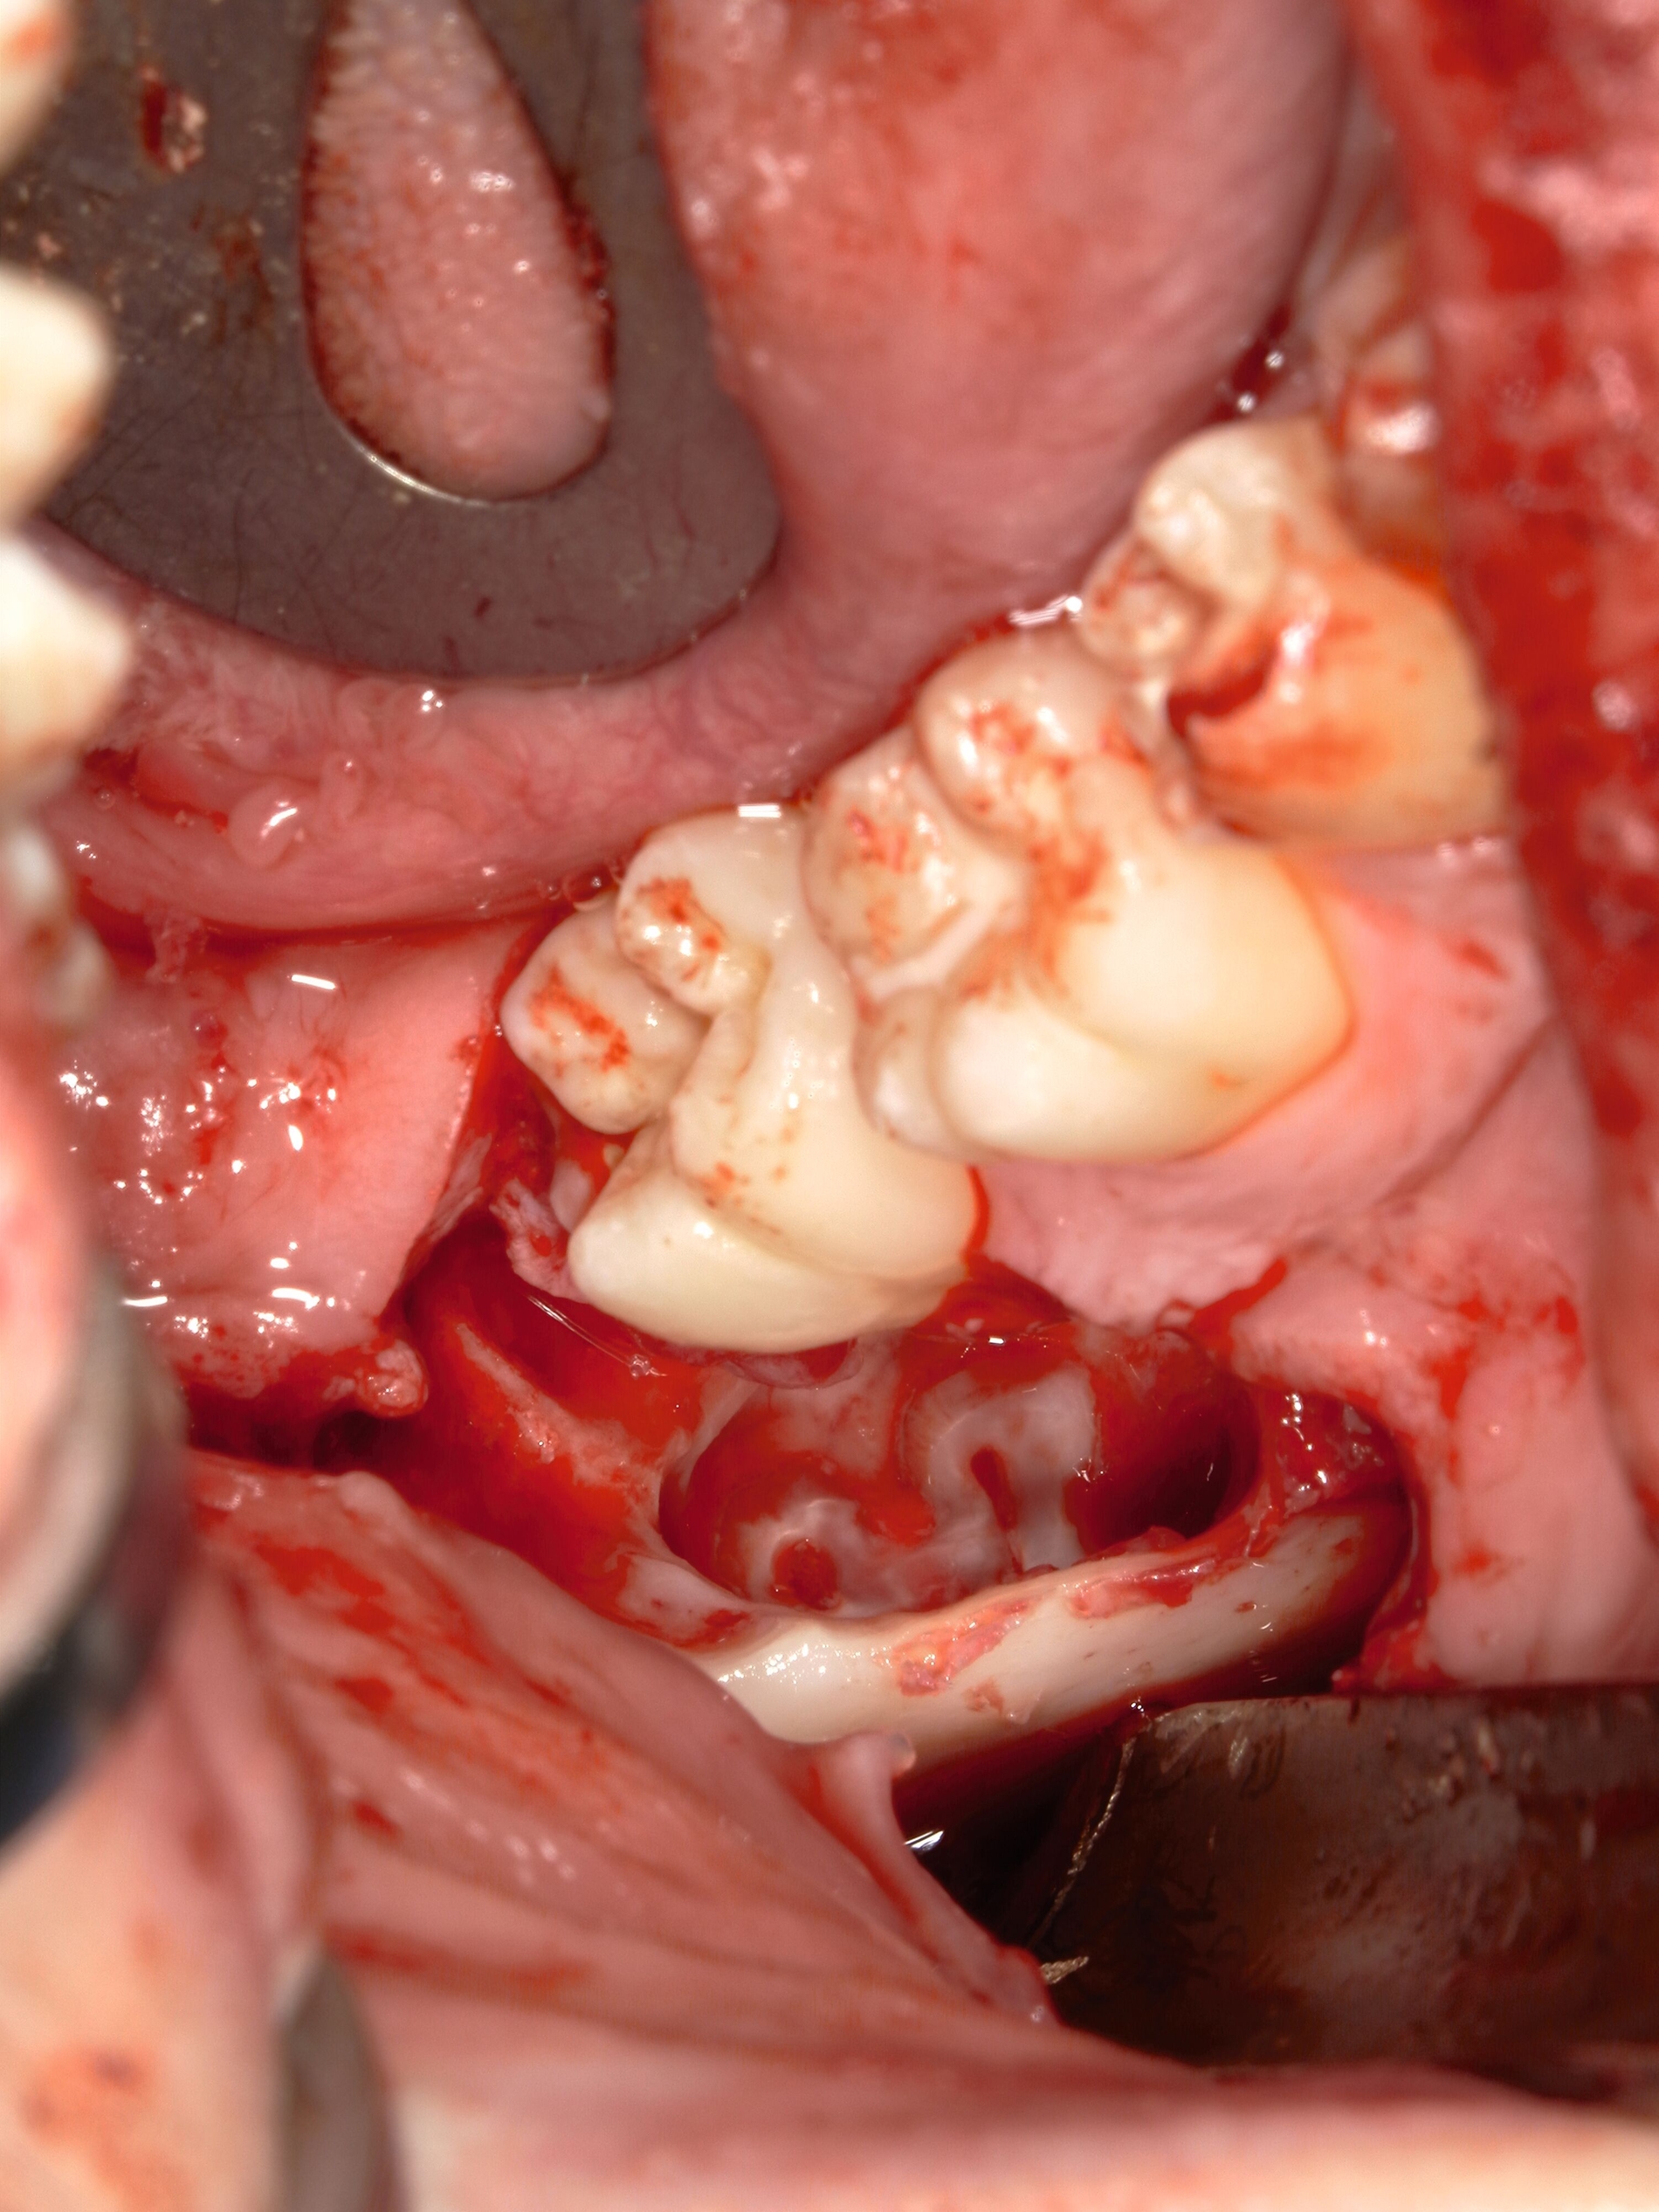

Nach Darstellung des Knochens kann der Weisheitszahn meist schon mit dem Hebel anluxiert oder mittels rotierendem Instrument freigelegt werden. Dabei muss möglichst oberhalb des Zahnäquators angesetzt werden, sonst kann der Zahn in die Kieferhöhle oder in das umliegende Weichgewebe luxieren. Anschließend erfolgen die Kürettage, die Entfernung des Zahnsäckchens, der Knochenkanten und des Granulationsgewebes sowie die Prüfung einer Mund-Antrum-Verbindung (MAV) mittels Bowman-Sonde. Bei positiver Testung erfolgt die plastische Deckung mittels Mukoperiostlappen oder bei ausgedehnteren Defekten mittels Bichat-Fettpfropf (Abbildungen 14 und 15) [Gutwald et al., 2019; Schwenzer, 2019].

Die Vorgehensweise ähnelt der konventionellen Weisheitszahnentfernung im Unterkiefer. Zunächst wird ein Mukoperiostlappen gebildet und die Zahnkrone freigelegt. An der größten Zirkumferenz wird diese mittels Lindemann-Fräse unter ständiger Wasserkühlung und anschließend mithilfe eines Bein´schen Hebels abgetrennt. Dabei sollte der Wurzelblock nicht anluxiert werden, da er sonst aufgrund eines erhöhten Infektionsrisikos entfernt werden muss. Alle Schmelzanteile werden entfernt, der verbleibende Wurzelblock und die Knochenkanten geglättet (Abbildung 16). Auf eine weitere Behandlung der Wurzelpulpen kann verzichtet werden [Wolf & Renton, 2016].

Nach ausgiebiger Kürettage, der Entfernung von Granulationsgewebe und Spülung erfolgt der Wundverschluss wie bereits beschrieben. Zur Kontrolle kann eine postoperative zweidimensionale Bildgebung durchgeführt werden (Abbildung 17), auch um zu beurteilen, ob alle Schmelzanteile der Zahnkrone entfernt wurden.